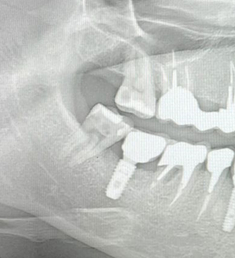

Январь 2023. Произошел спор с пациентом, который 4 месяца назад удалил зубы в городской поликлинике, где ему разворошили всю кость и он был очень удивлен, почему мы не сможем сходу установить импланты без наращивания. Этой ситуацией хотелось с кем-то поделиться, причем с тем, для кого это не рутина. Я вспомнил про свои посты. И меня понесло. Начал писать статьи одну за другой. И в какой-то момент я заметил, что чем больше я пишу, тем больше народ начинает задумываться о своем здоровье. Люди стали засыпать меня вопросами, я по мере возможности отвечал, иногда совсем поражался тем, насколько люди у нас не просвещены в этом плане. Стало поступать множество призывов помочь, просили персональной консультации.

Кидаем снимки, если есть.

Если есть КТ, то кидаем на почту vadbel1310kt@yandex.ru В теме письма указываем ваш никнейм телеграме, чтобы я мог понять кто это прислал, посмотреть и ответить.